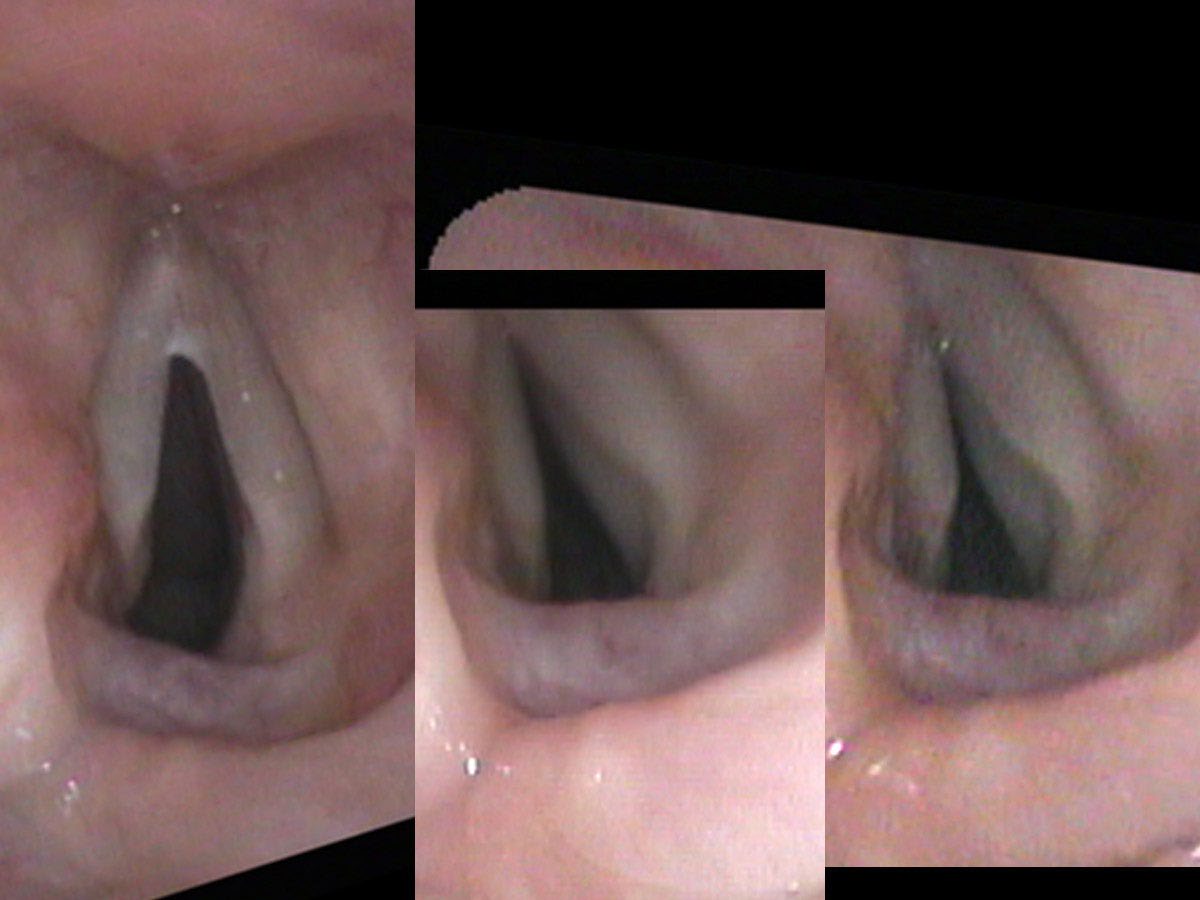

On her endoscopic exam, the healthy right vocal cord opened and closed appropriately, both during breathing and during sound production. She had quite a strong voice, though I would say that it actually had a too tight, strained quality. During the ultra-close portion of my endoscopic exam, I touched the left, non-moving or “paralyzed” cord lightly and it suddenly moved across the midline nearly closing off her airway. It wasn’t paralyzed; it could move. It just did not move intentionally and appropriately during breathing or during phonation and it was trigger-happy. With even a small trigger, her left LCA muscle would spasm and move the left vocal process nearly all the way to the opposite cord.

As both treatment and a test, I injected botulinum toxin into her dyskinetic (actually the opposite of paralyzed — hypercontracting), left vocal cord. Specifically, I put it into the TA and LCA muscles — the muscles that tense and move the cord toward the midline and closure. Two weeks later, the opening in her larynx was larger while she was breathing. She could still make sound, though a little more softly. However, she could breathe better than she had in several years and she had not had any further laryngospasms since the injection.